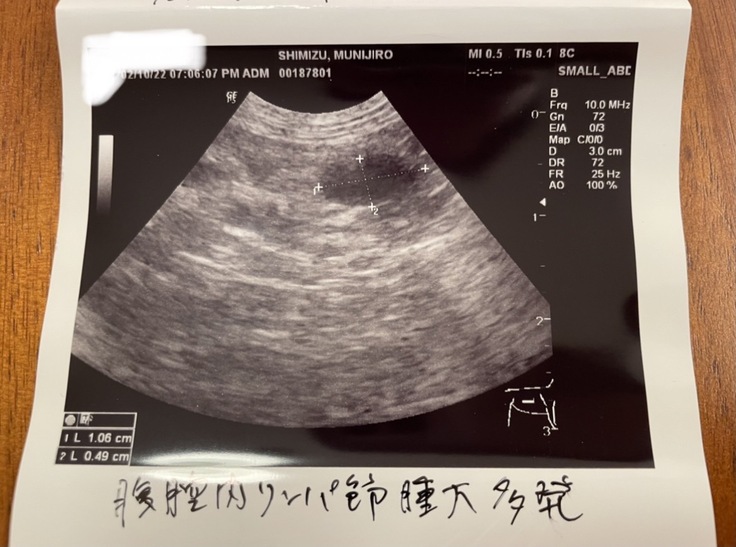

<エコー写真とPCR結果>

血液検査の結果と、腎臓と腹腔内のリンパ節が肥大していることから、FIPの可能性が高いと診断されました。

結果的に腹腔内のリンパ節からはネココロナウイルスは検出されませんでしたが、それでもFIPの可能性が非常に高いことから、試験的に未承認薬を投与する治療を開始したところ、少しずつ回復してきています。(2022年3月9日時点)